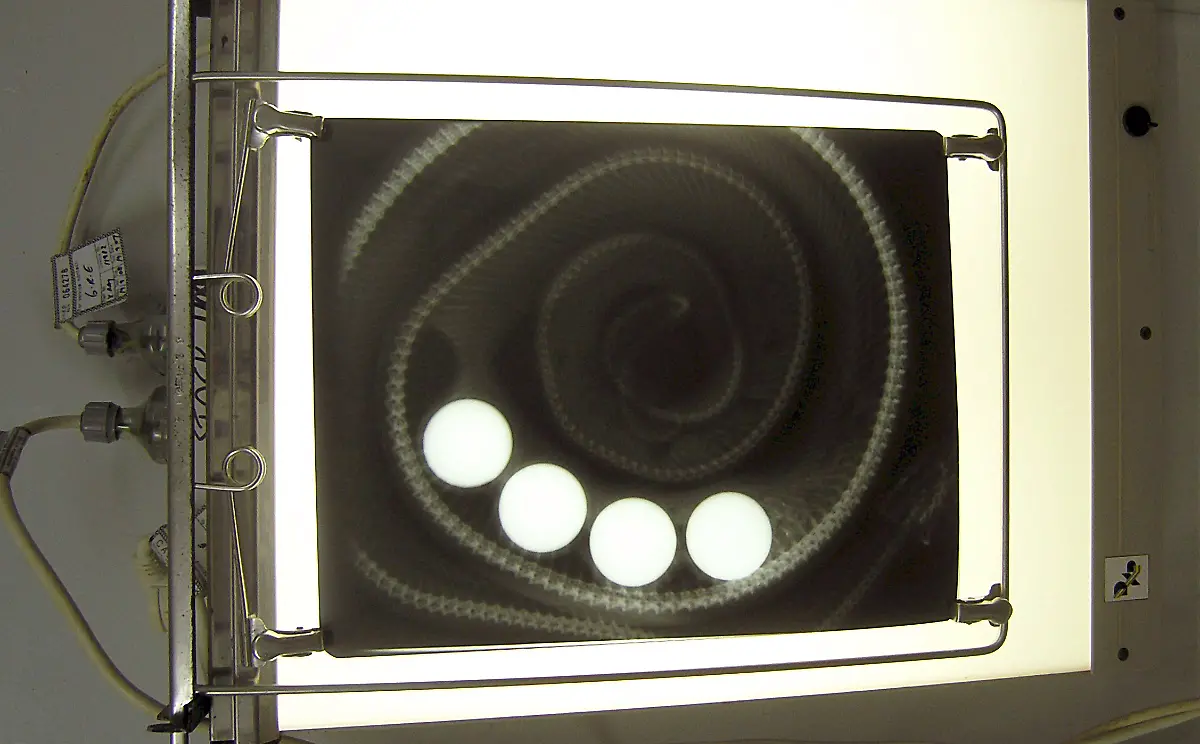

Socken, Kieselsteine, Außerirdische - Röntgenbilder von Mägen US-amerikanischer Haustiere zeigen die skurrilsten Gegenstände. Eine Zeitschrift zeichnet jedes Jahr die außergewöhnlichsten Aufnahmen aus.